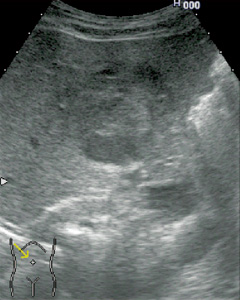

■ Flash機能とMicrobubble Trace Imaging(MTI)(図3)

体内に貯まったソナゾイドは,高音圧送信することで破壊することができる。

Flash機能は高音圧送信でソナゾイドを破壊し,再環流を観察する機能である。また,MTIは,造影剤による高輝度部を重ね合わせる画像で,血管像の観察に適している。

図3 HCCのMTI像 (画像ご提供:三重大学 田中秀明先生)

a:MTI像

b:LowMIでのFundamental像